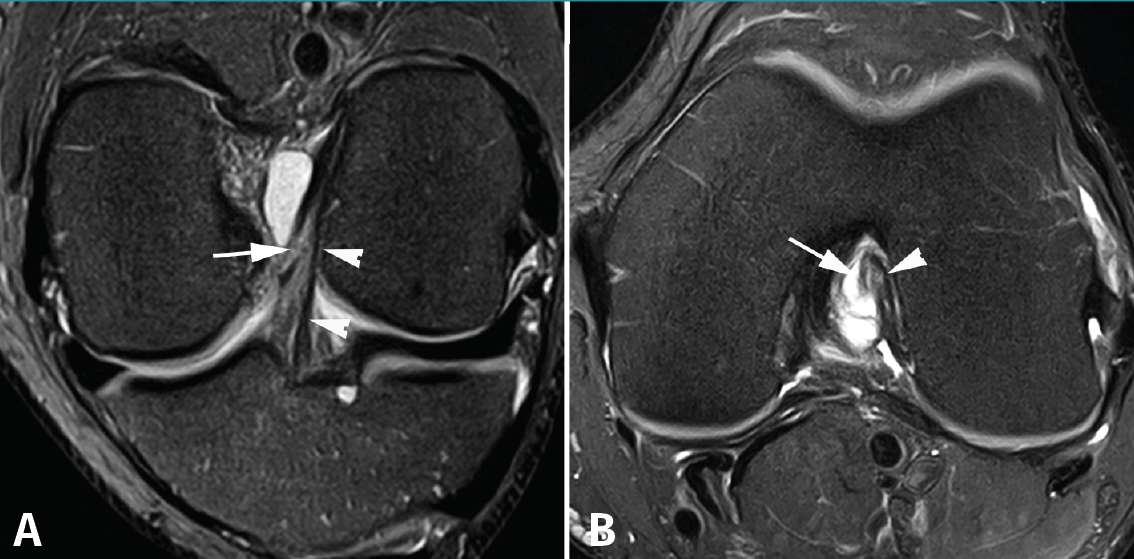

Los hallazgos de RM en las roturas parciales del LCA consisten en un aumento de la señal intrasustancial, defectos focales, distorsión y atenuación de fibras o una orientación anormal del ligamento(1,16)(Figuras 4 y 5). El diagnóstico es más sencillo en fase aguda, por la presencia de signos secundarios con edema y derrame articular. La principal dificultad diagnóstica con RM en la fase aguda consiste en diferenciar roturas parciales de alto grado de completas(1,16).

Figura 4. Rotura parcial del fascículo anteromedial (AM) del ligamento cruzado anterior (LCA) con formación de pequeño ganglión en la escotadura intercondílea. Corte oblicuo coronal (A) y axial (B) de resonancia magnética (RM) potenciados en densidad protónica con supresión grasa que muestran una rotura del fascículo AM (flechas). Fascículo posterolateral normal (cabezas de flecha).